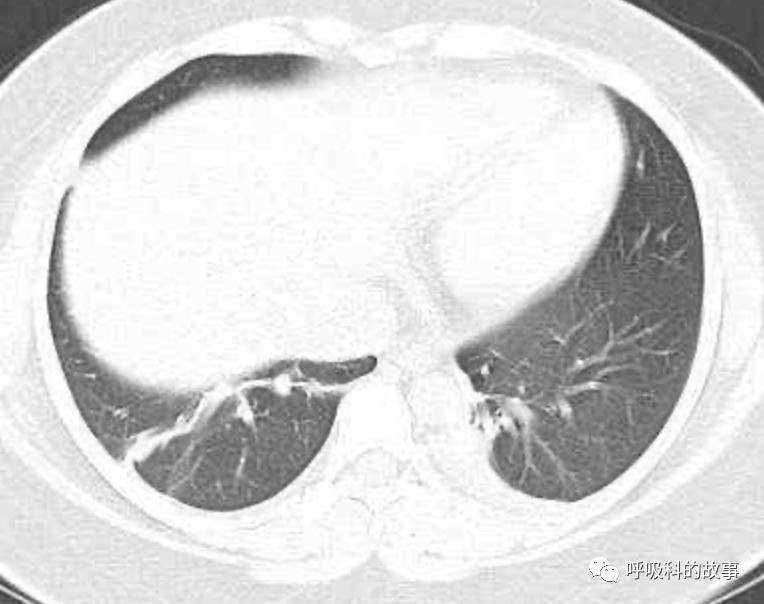

患者发热后行胸部CT检查(6月21日,住院第13天),可见两下肺有条片影,当时考虑是肺炎引起的发热。

可是在6月26日(往院第18天)仍持续发热的情况下复查肺部CT,肺部病灶已明显吸收了。那么患者发热的原因到底是什么呢?为什么患者高热的情况下血白细胞不升反降,C反应蛋白也没有明显增高?这个时候消化科医生也迷茫了,这可怎么办?于是请感染科和呼吸科医生一起会诊,共商计策。